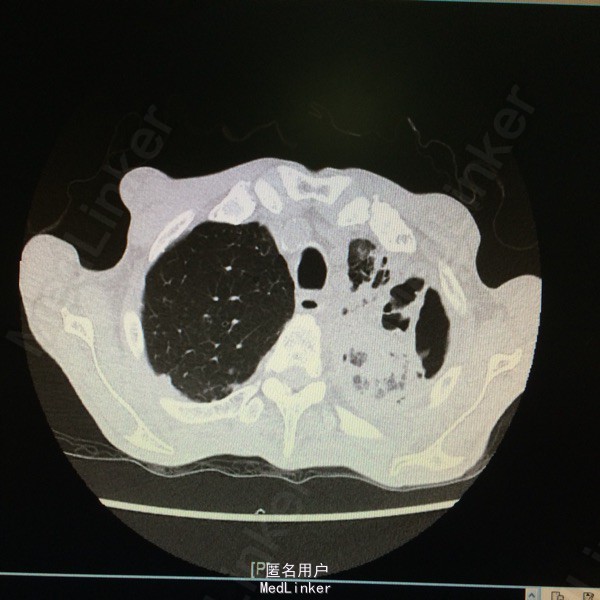

查体:T37.7度,P130次/分,BP 77/59次/分,神情,恶病质,双肺呼吸音粗,未及干湿罗音。 辅助检查:胸部CT示:双肺感染、左肺实变部分坏死。支气管镜示:左上叶气管黏膜感染:真菌?结核?黏膜病理报:符合真菌感染,形态学考虑为曲菌。多次痰培养示:曲霉菌感染。白细胞 12.9*10E9/L,CRP 140ng/ml,ESR 140mm/h,PCT 0.676ng/ml。

随访:患者现予“伏立康唑、两性B”治疗,体温正常,咳嗽咳痰明显好转。复查胸部CT示:左肺上叶病变较前进展,下叶病变较前吸收,左肺实变部分坏死空洞范围较前扩大。 讨论:据痰培养及病理,可明确诊断“肺曲霉菌感染”;予两性霉素B治疗后体温可降至正常,支持该患者发热为曲霉菌感染所致。痰培养及病理结果均支持曲霉菌感染的病例还是少见的。就患者体温变化而言,示治疗有效;其胸部CT示左肺坏死空洞较前扩大,其左肺大部分为坏死组织,空洞会随着这些组织的排出而变大。